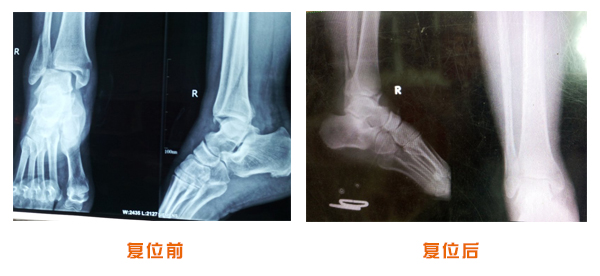

肥城市安駕莊梁氏骨科醫院是一所以梁氏手法正骨配合膏藥為特色的現代化??漆t院。

梁氏骨科術始創于清雍正年間,歷經八代,至今已有三百年歷史。據1929年泰安縣志載“梁瑞圖先生,字增生,號蓮峰,安駕莊人,精岐黃并發(fā)明接骨,凡跌打車凡跌打車軋皮不破而碎骨者......【詳細】 |